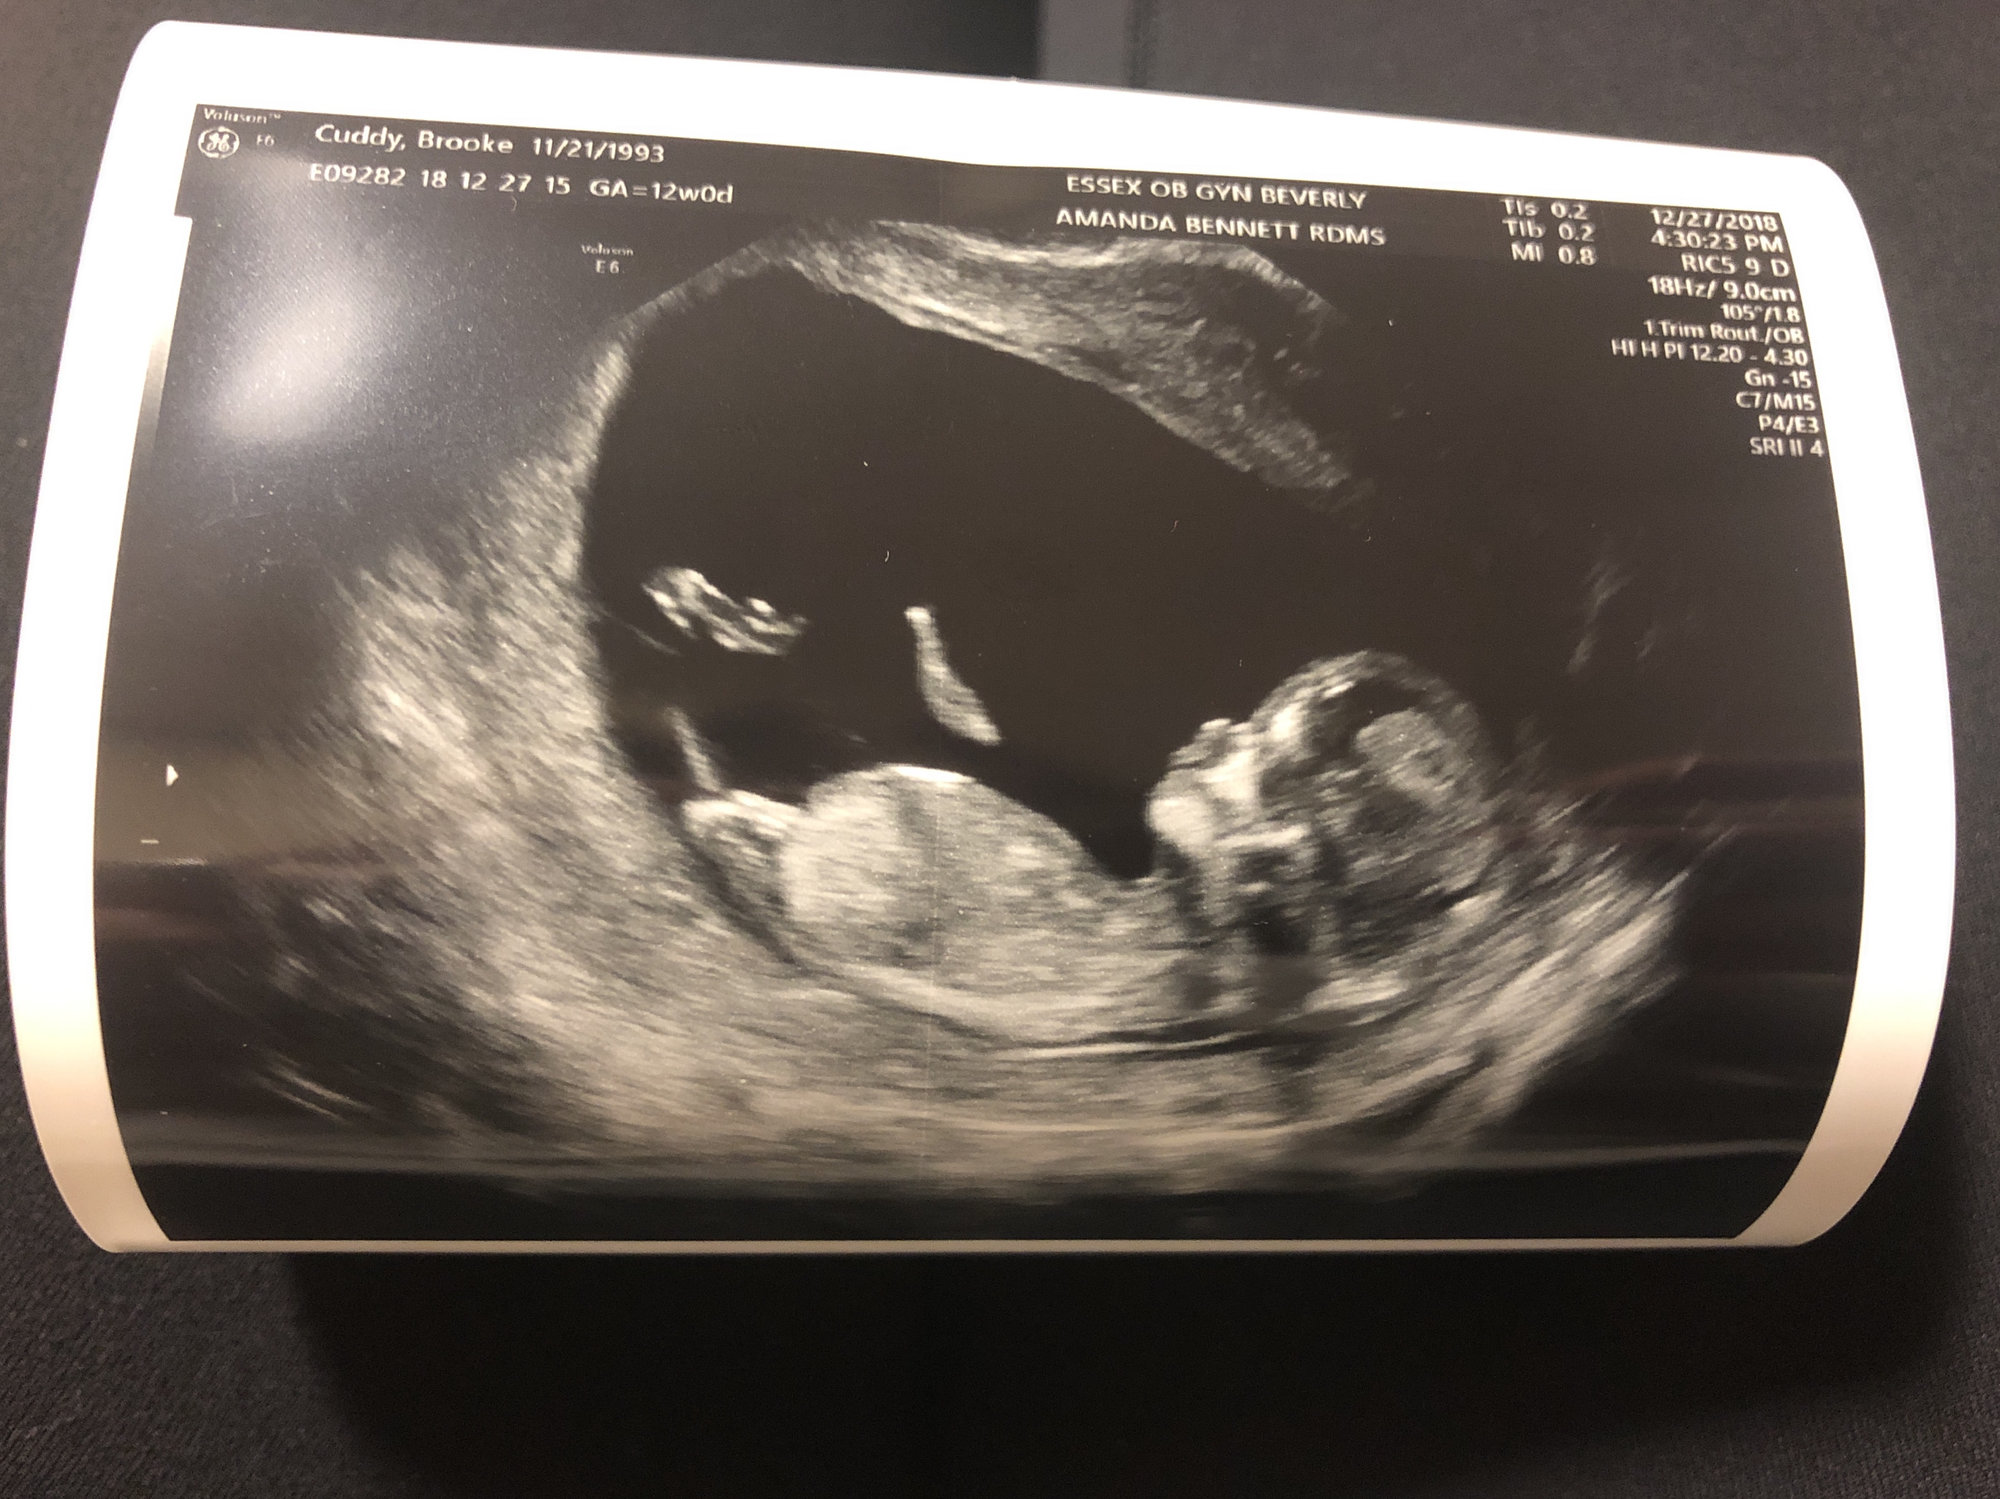

• 12 weeks 4 days!!

• It’s amazing how clear the ultrasounds get at 12 weeks!